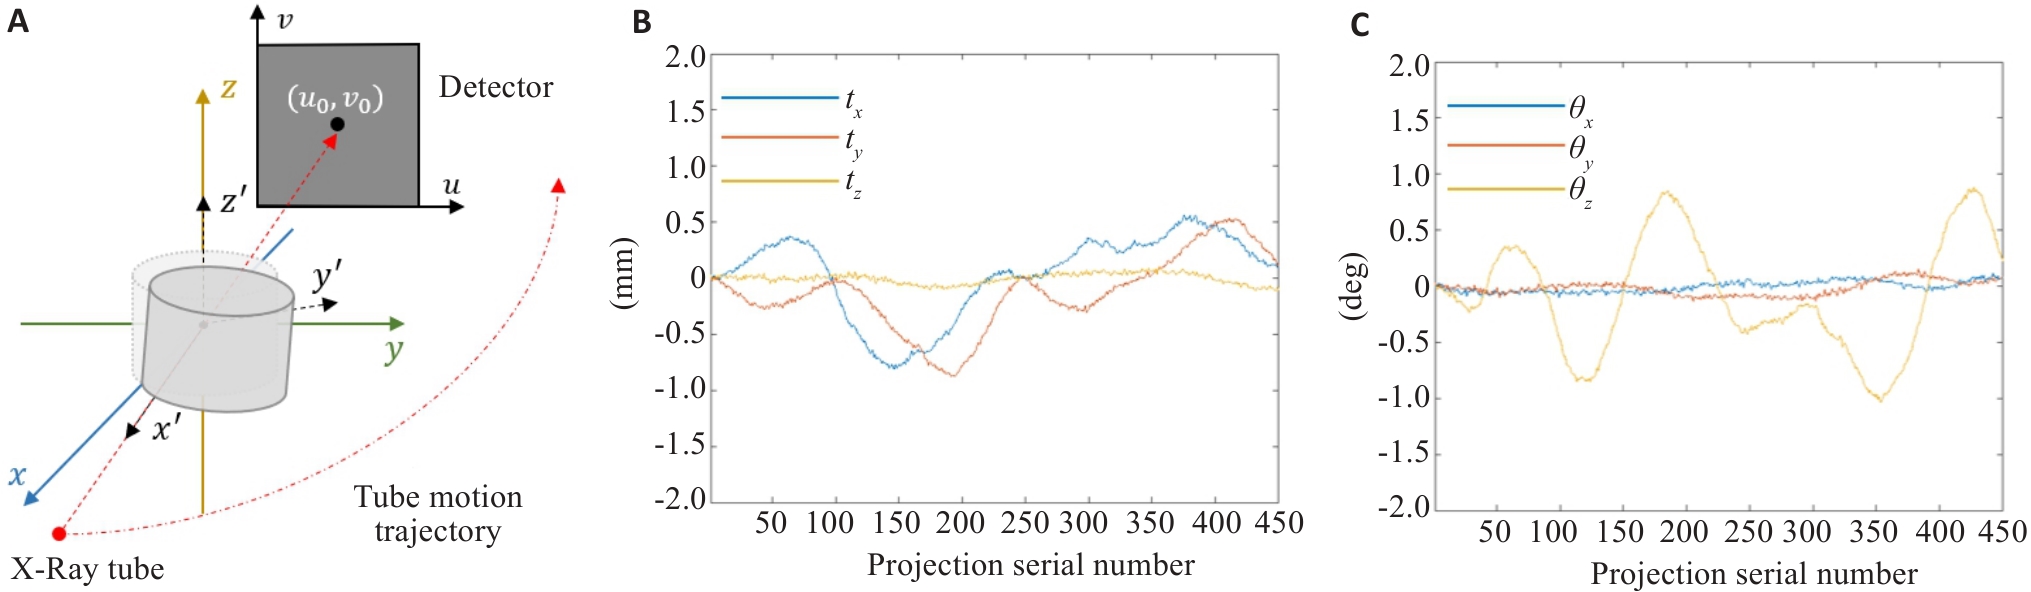

Fig.4 Schematic diagram of CBCT scanning and motion waveforms. A: Schematic diagram of CBCT scanning. B: Translational motion waveform used in the simulation. C: Rotational motion waveform used in the simulation.